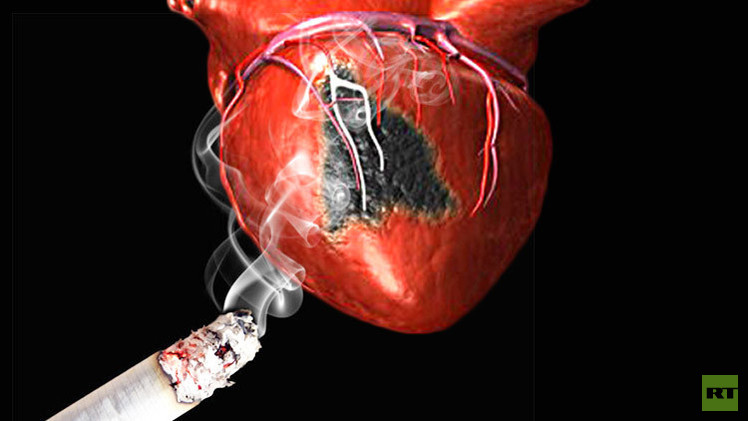

بعد النوبة القلبية.. ترك التدخين يحسن الصحة العقلية أيضا

أظهرت دراسة جديدة أدلة تفيد بأن ترك التدخين بعد الإصابة بنوبة قلبية يشكل دفعة قوية لتحسين الصحة العقلية، عدا عن الآثار الإيجابية المباشرة على الصحة العامة.

ويعاني المدخنون بعد النوبة القلبية من آلام صدرية وخمول عام وضعف في العمليات الحيوية. وفي حال عدم تركهم للتدخين بعد الإصابة بالنوبة، تستمر صحتهم العامة بالتراجع التدريجي حتى لو ظهرت علامات التعافي على عمل القلب. وبحسب الدراسة فإن المدخنين الذين تركوا التدخين بعد النوبة مباشرة، أظهروا تحسناً سريعاً في أعراض ما بعد النوبة، إضافة إلى تحسن ملحوظ في صحتهم العقلية.